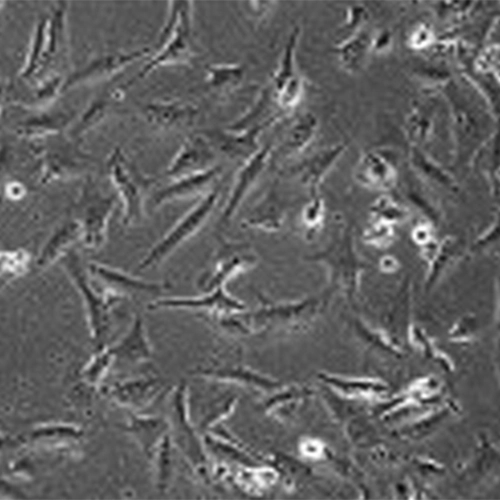

Studies of follicle development and toxicology have been assisted by the use of in vitro cultures of ovaries or follicles. According to a 2014 published article in Reproductive Toxicology by Stefansdottir and team, the parameters of ovary cells culture can be controlled precisely to permit an in-detail analysis of the toxic effects of a molecule. The way a molecule targets the follicles or chromosomes or signalling can be highlighted. The approach to culture depends on the species of study and media used. The direct effects of toxins can be studied using embryonic culture or pre-meiotic germ cell culture.

Many studies have shown that the effects of compounds are highly similar for in vitro and in vivo studies though the study designs can be different.